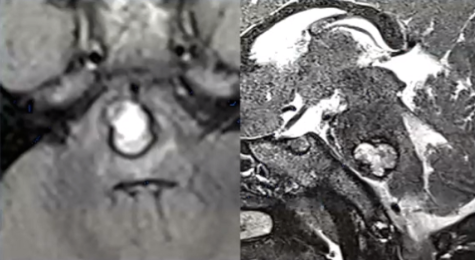

三岁半女童安妮:巨大血肿病例,教授通过颞下入路抵达桥脑侧面,完全清除血肿的同时完好保留桥脑后部结构。